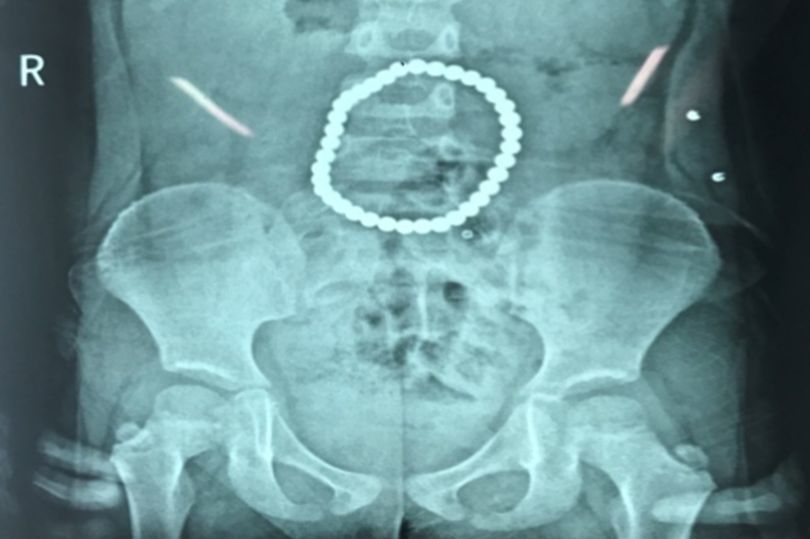

| Hình chụp phim cho thấy chuỗi nam châm nằm trong người bé gái |

Hình ảnh chụp phim từ bệnh viện cho thấy các viên bi đồ chơi hiệu BuckyBall đã hút nhau bên trong dạ dày cô bé và tạo thành một vòng tròn.

| Các viên bi hút nhau tạo thành một vòng tròn như chiếc vòng đeo tay |